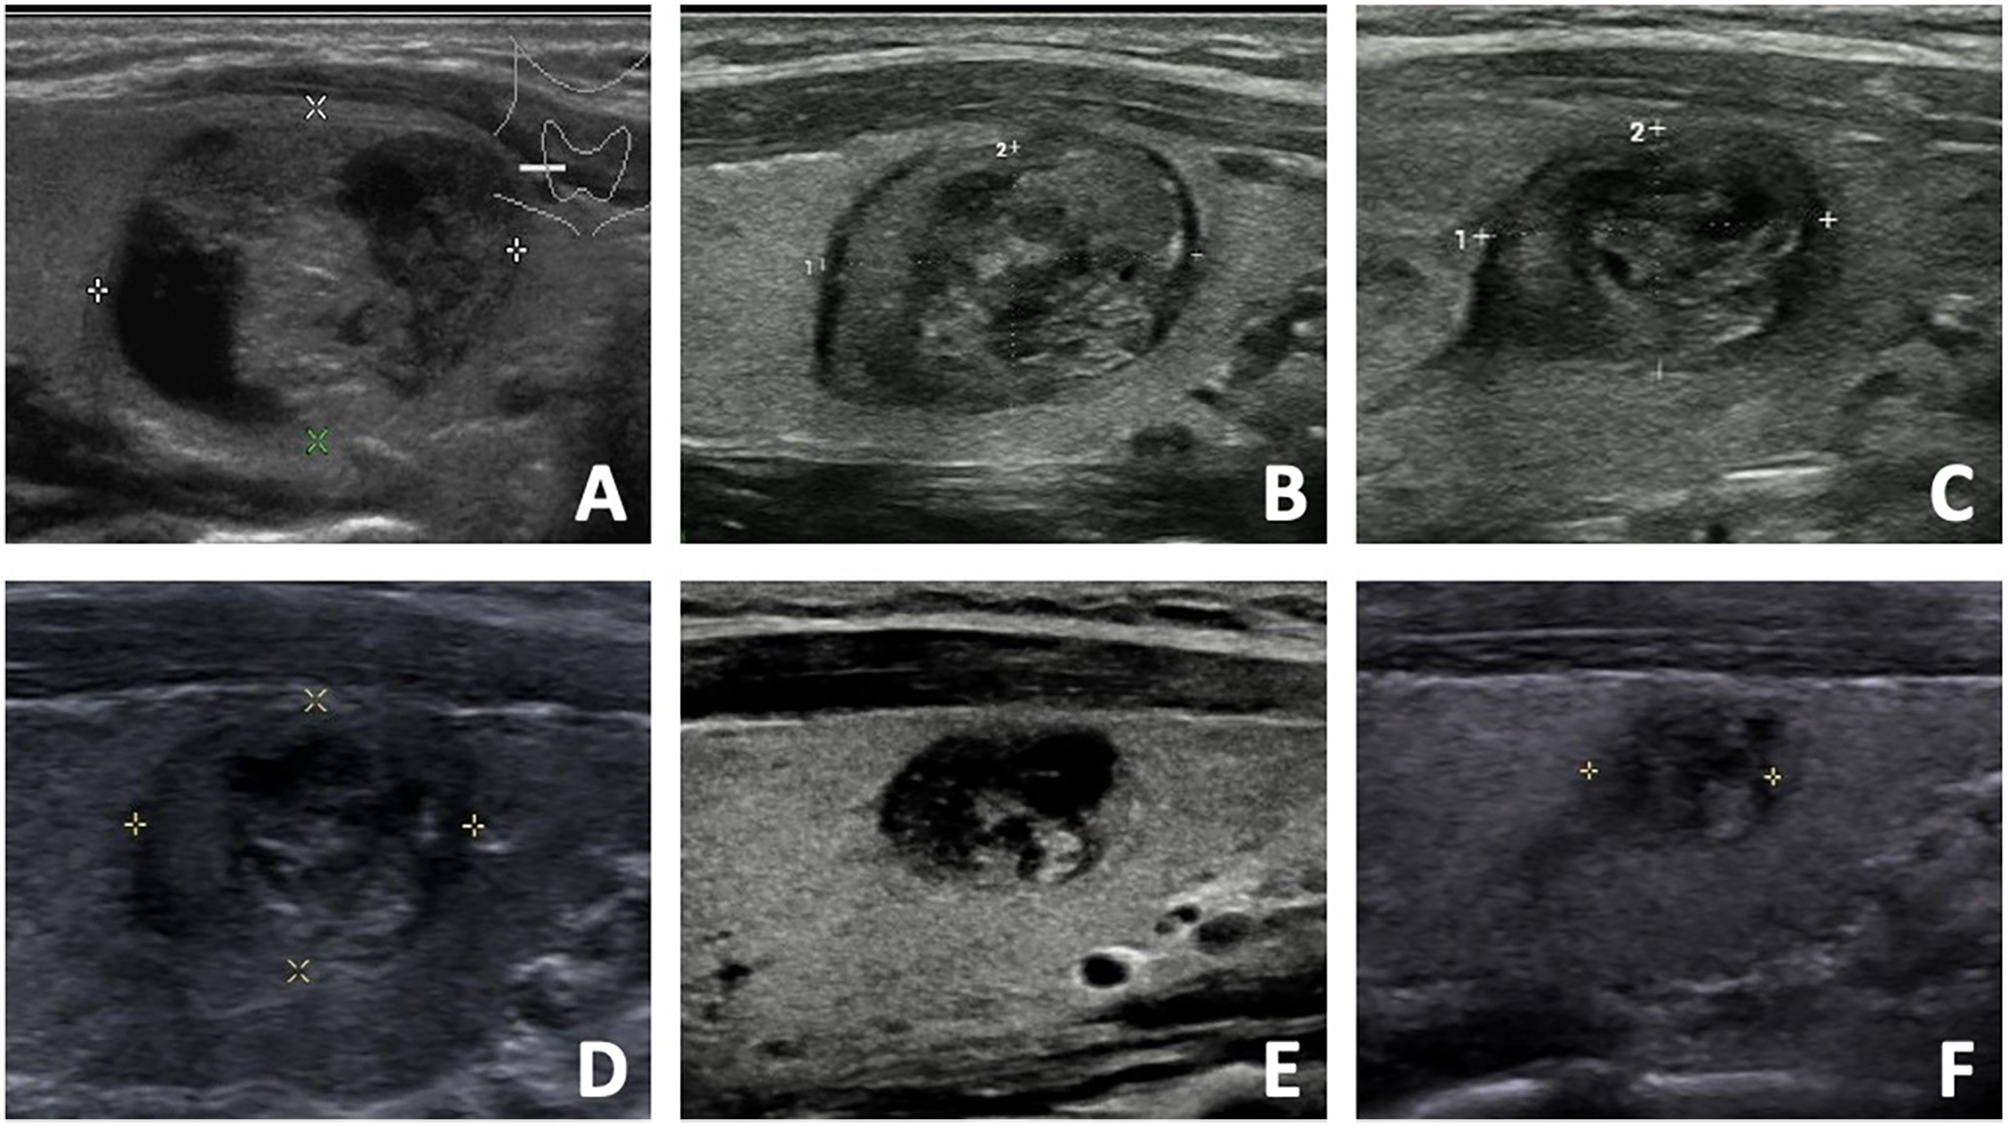

Regrowth was observed in 30 out 220 nodules (13.64%), which all occurred in the untreated peripheral area. The mean timing of regrowth was at 22.40 ± 12.10 months after RFA. All the regrowth nodules underwent additional RFA. The changes of volume and VRR in the two groups are present in Table 2. In the first 12 months, VRR in the two groups were nonsignificant (all P >0.05). However, at 24 months after RFA, VRR in the non-regrowth group were significantly larger than that in the regrowth group (90.39 ± 11.23% vs 78.65 ± 12.24%, P = 0.002) (Figure 1). A total of 7 nodules had volume reduction less than 50% at 12 months. Five nodules were in the regrowth group and 2 in the non-regrowth group (16.67% vs 1.05%, P <0.001). Representative cases in the two groups are shown in Figures 2, 3.

Figure 3 The US images of a 33- year-old female with a benign thyroid nodule in the non-regrowth group. (A) The initial volume of nodule was 5.32 ml before RFA. The nodule was located in the normal location, and the vascularity was grade 1. The risk of regrowth by the nomogram was 2.1%. (B) At 1 month after RFA, the volume was 1.58 ml and VRR was 70.30%. (C) At 3 months after RFA, the volume was 0.88 ml and VRR was 83.46%. (D) At 6 months after RFA, the volume was 0.76 ml and VRR was 85.71%. (E) At 12 months after RFA, the volume was 0.32 ml and VRR was 93.98%. (F) At 18 months after RFA, the volume was 0.18 ml and VRR was 96.62%.